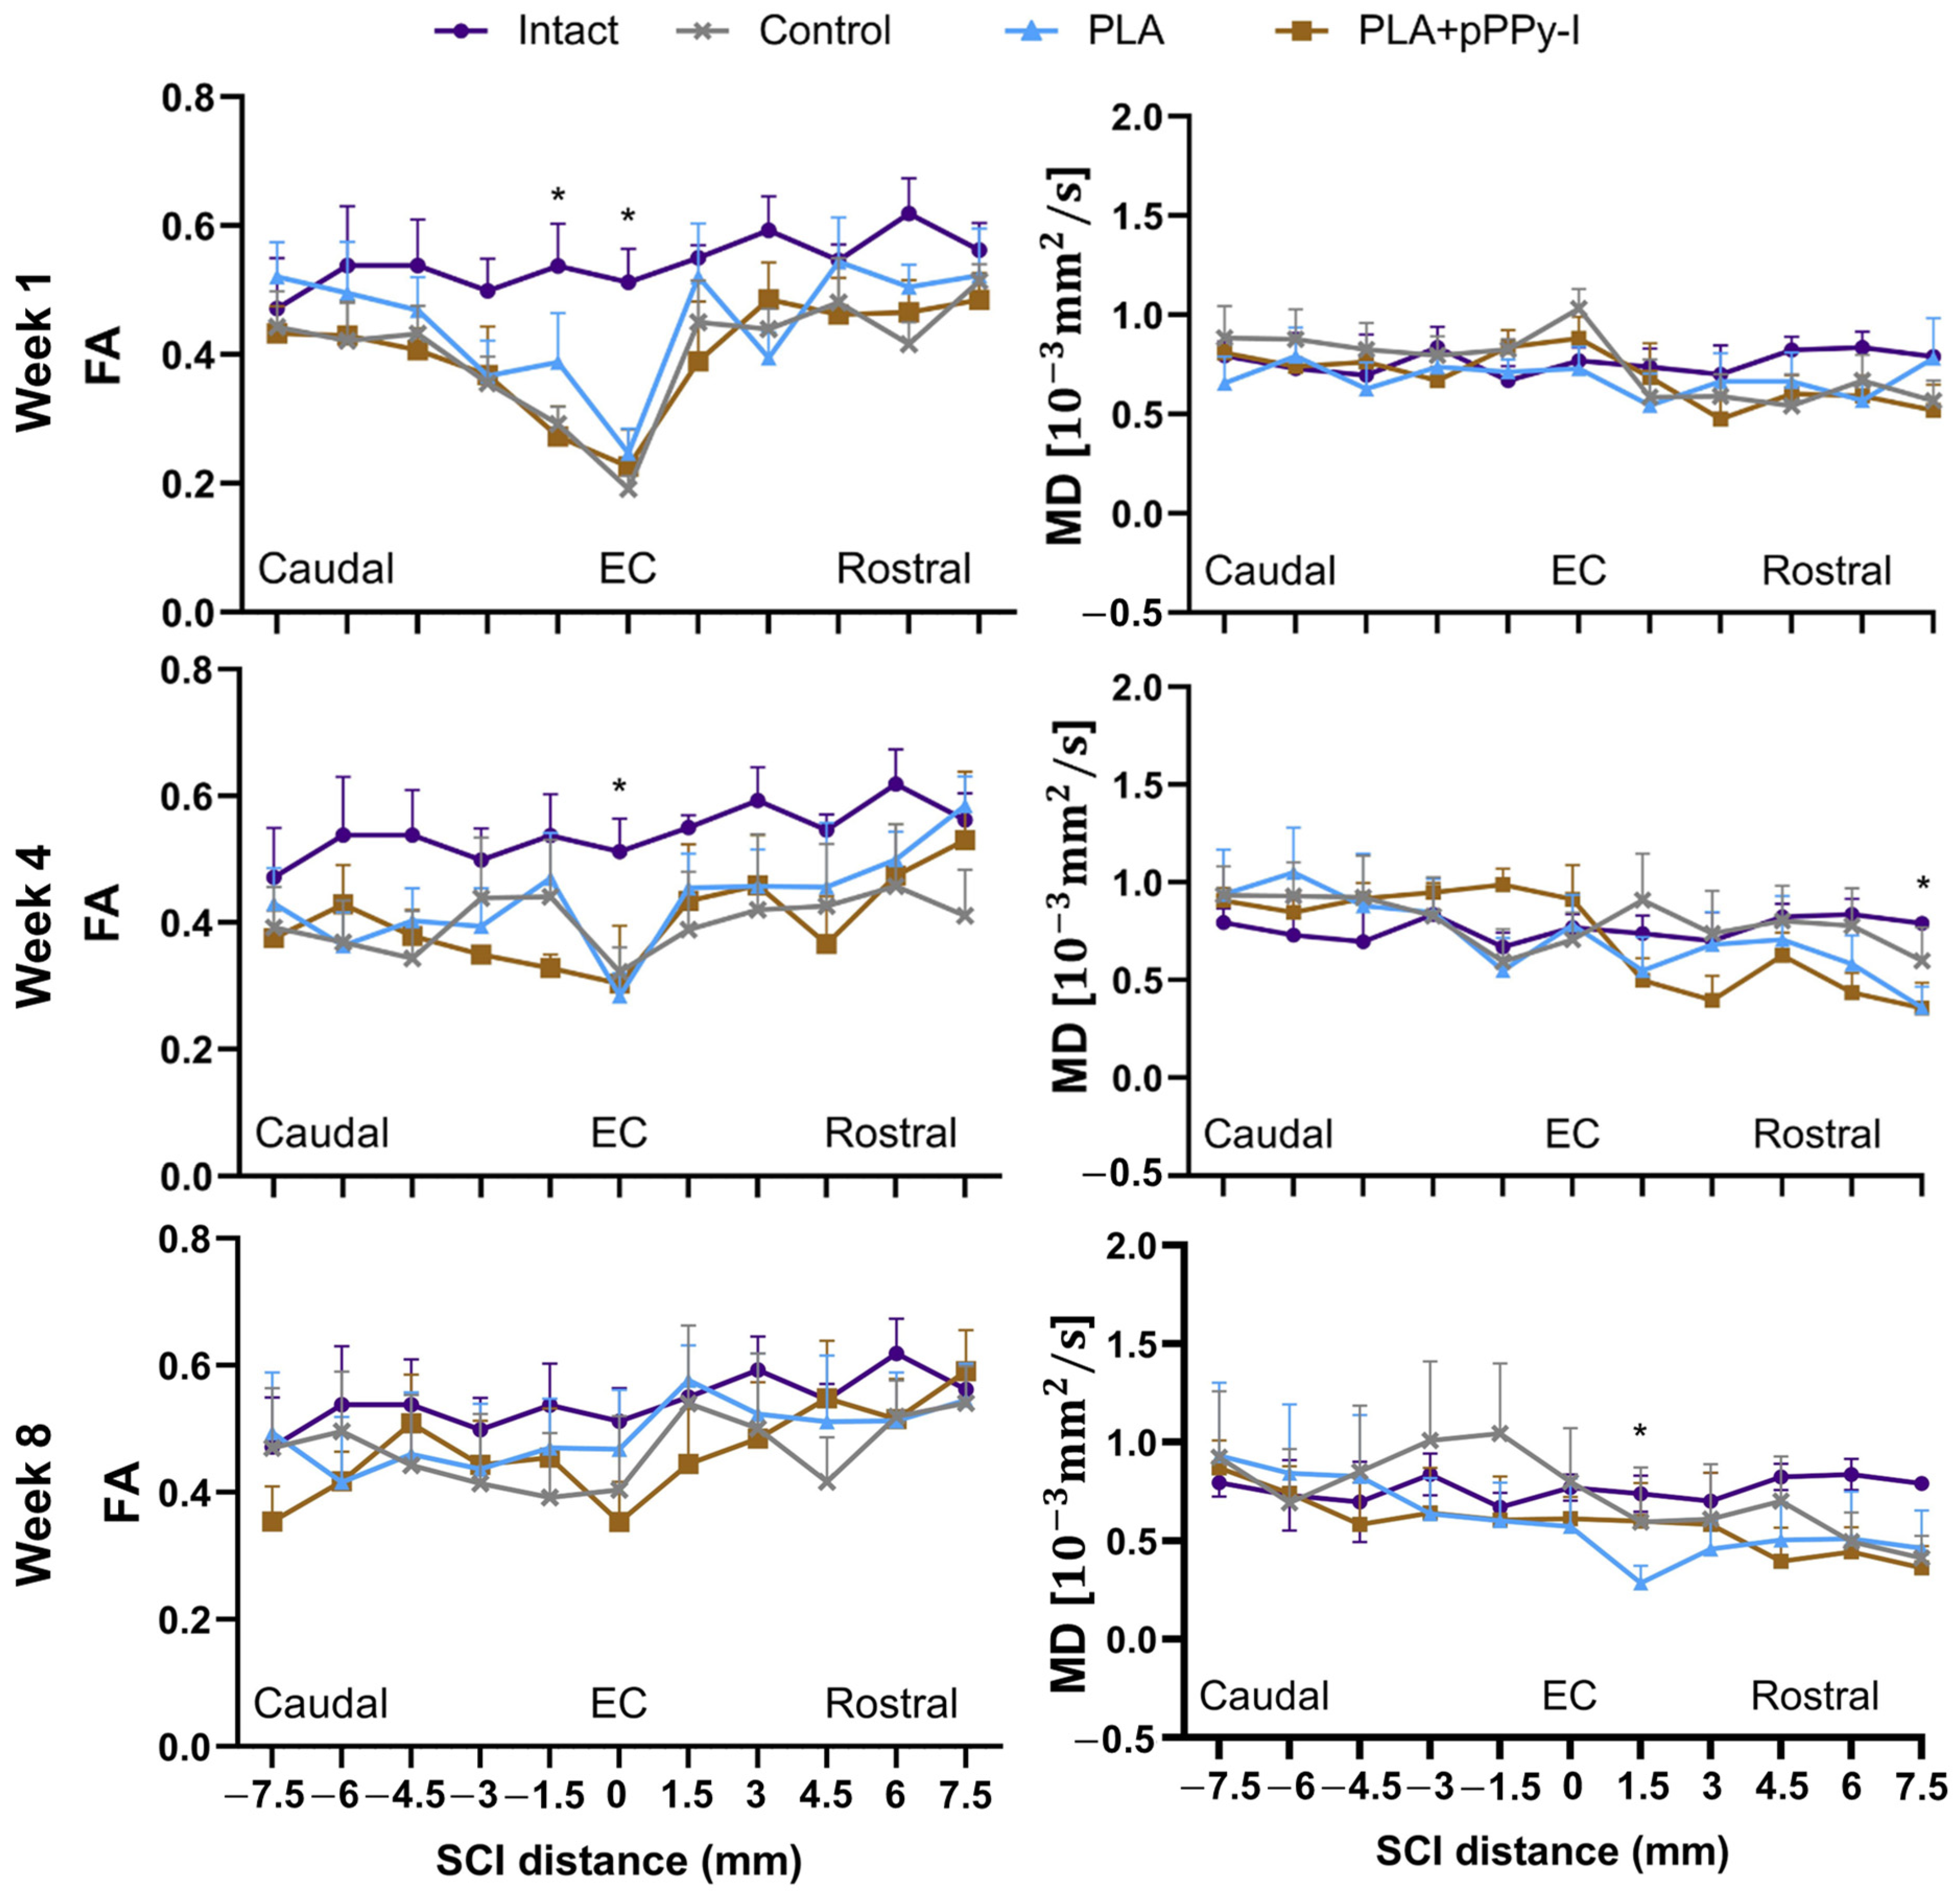

3.5. The Recovery of Anisotropy Baseline Values Suggests Neural Pathway Reorganization across the Scaffolds